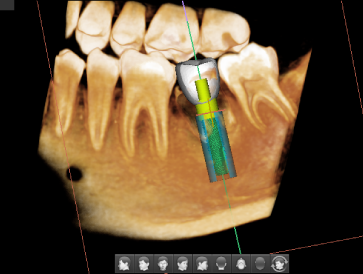

Эндо и одиночный имплантат

5x5

Оптимальный размер для исследования области из 3-4 зубов

Артефакты от металлов мешают визуализации и естественным образом снижают достоверность диагностики. Четкие изображения дают вам меньше поводов волноваться и больше доверия к результатам диагностики при планировании имплантации. А также вам не составит труда планирование хирургического шаблона.

• Достаточный уровень детализации для создания хирургического шаблона

Подбор имплантата и визуализация размещения